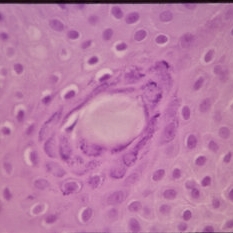

Histopathology of Linear Sebaceous Nevus Syndrome

Histopathology of Linear Sebaceous Nevus Syndrome

Feb 20 2015 by H. Michael Lambert, MD

Histopathology of linear sebaceous nevus syndrome.

Condition/keywords: histopathology, linear nevus sebaceous syndrome